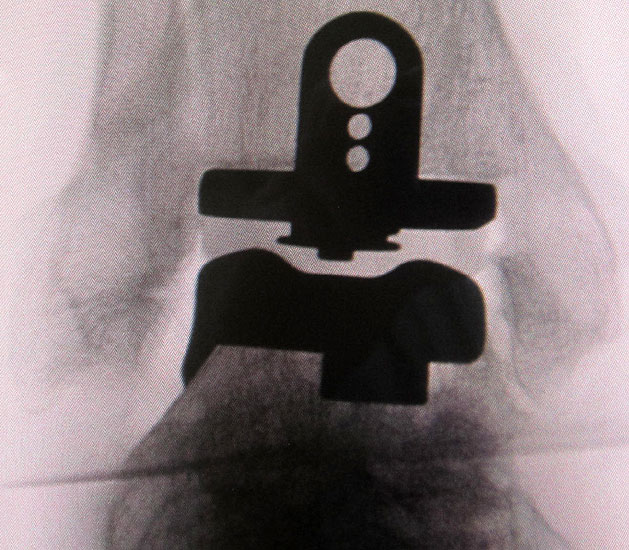

• Prothesenplanung anhand von Röntgenschablonen (Abb. 1 und 2).

• Instrumentarium SALTO II/Talaris